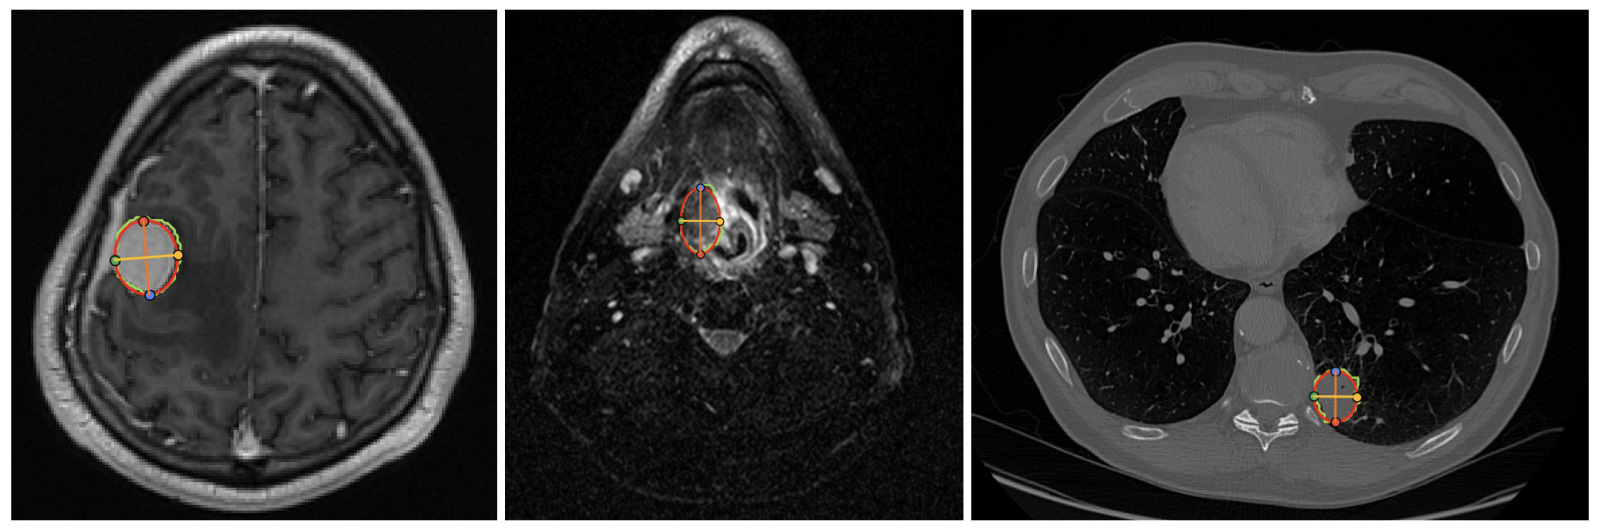

VLMs are asked to estimate the longest diameter and its perpendicular diameter of tumors/lesions. An example of the quantitative annotations from this work is shown below.

Figure 2: Tumor/lesion size annotation. An ellipse is fitted to the tumor/lesion mask and 4 landmarks are recorded.